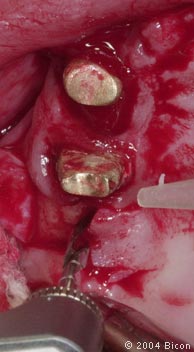

9. |

根管治疗失败的牙齿。 |